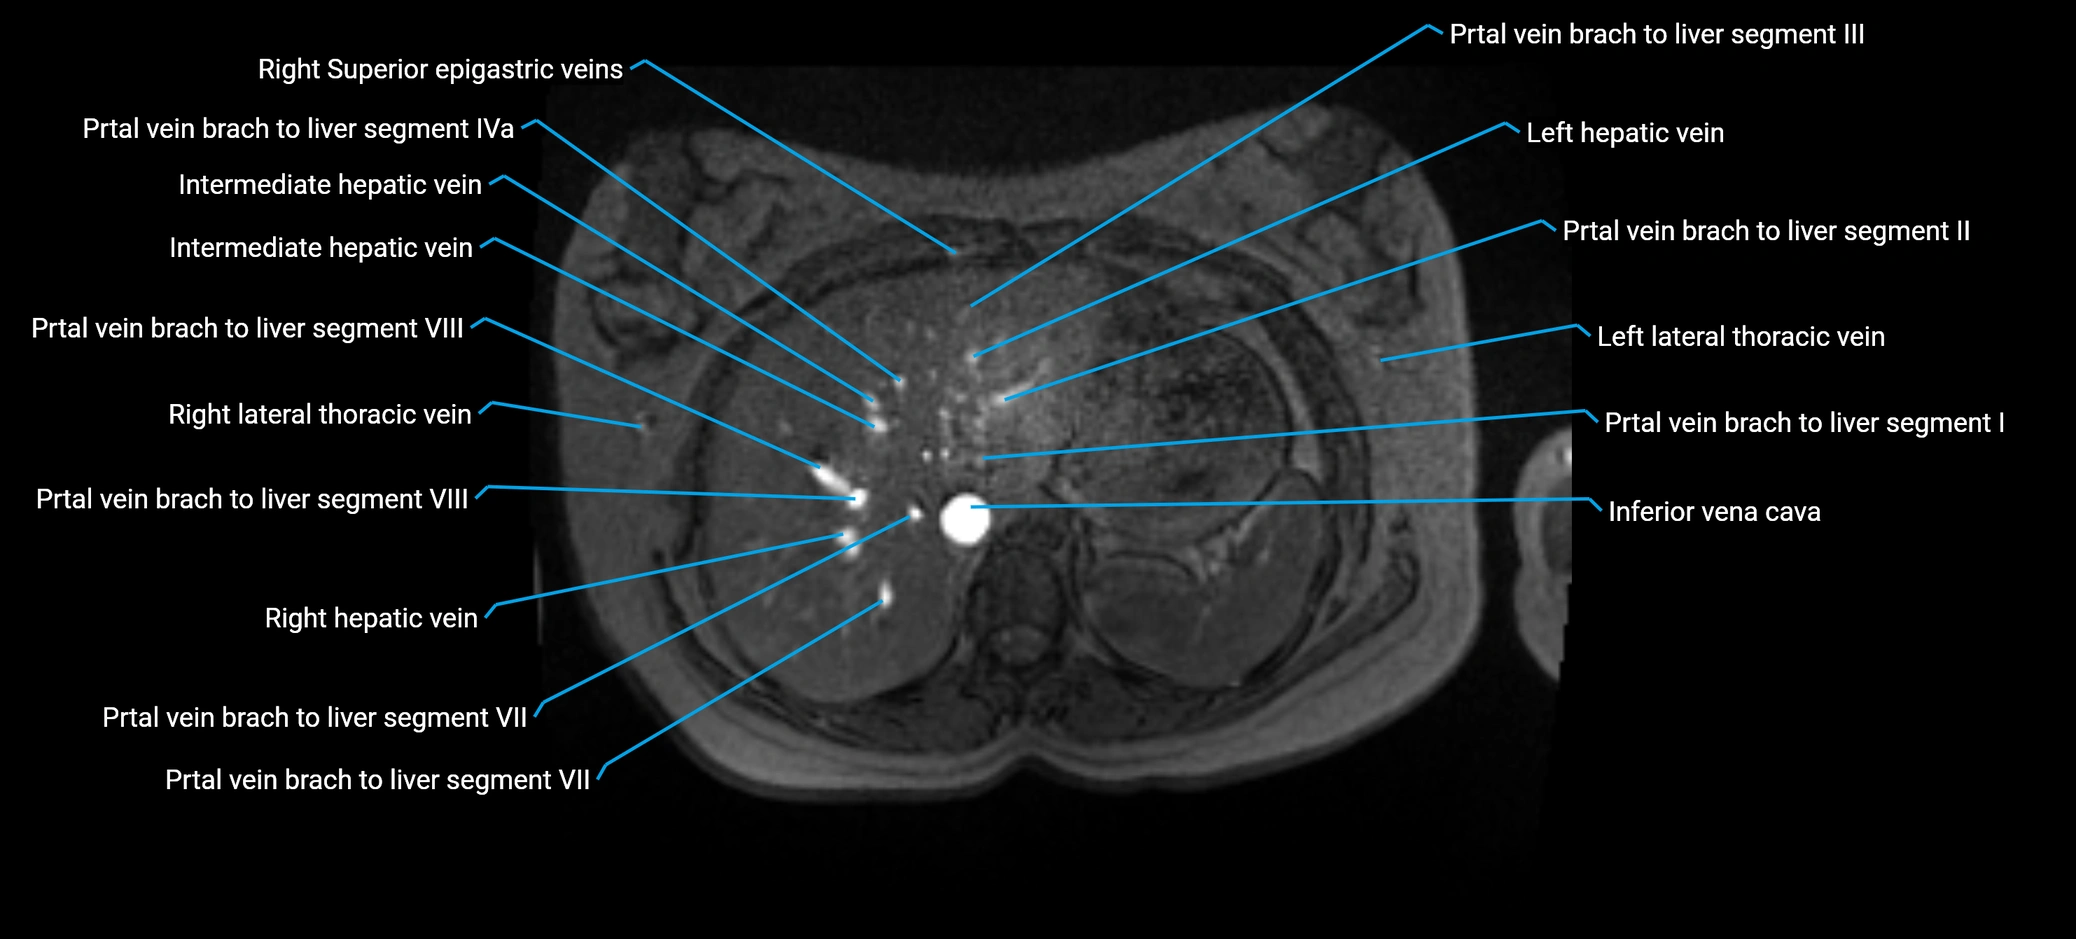

MRV TOF (Time-of-Flight MR Venography):

• Appears as a bright, high-signal vascular channel representing flowing blood

• Clearly shows branching pattern of right portal vein into anterior and posterior branches

• Best in coronal or axial reconstructions for segmental mapping

• No need for contrast, relies on flow-related enhancement

MRI image

image